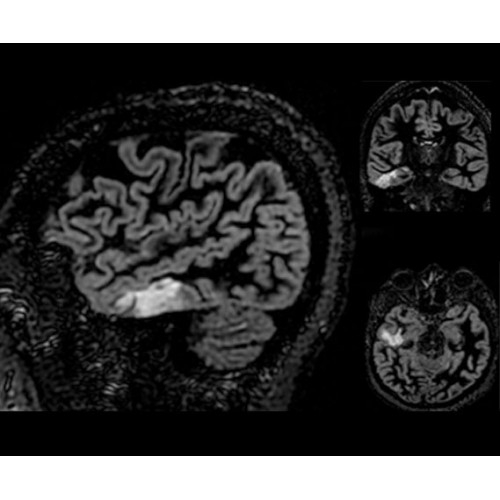

• Специальный пакет приложений для измерения и сравнения объемных изображений ЦНС с нормами поможет вам в диагностике нейродегенеративных заболеваний, а дополнительные инструменты визуализации — в постановке точного диагноза с помощью бета-амилоидов и радиоизотопных маркеров ФДГ.

Кроме того, в результате использования технологии TOF и инновационной технологии реконструкции Q.Clear вы сможете добиться прекрасного соотношения сигнал/шум. А благодаря технологии нулевого времени эхо (ZTE) визуализировать костную структуру без ионизирующего излучения. Все эти разработки для улучшения качества сканирования и точности анализа помогут вам использовать весь потенциал ПЭТ/МРТ.

• МРТ с функцией нулевого времени эхо (ZTE) отличается точностью, возможностью персональных настроек и отсутствием ионизирующего излучения. Она приходит на смену традиционному исследованию на основе рентгеновского излучения. МРТ с функцией нулевого времени эхо (ZTE) на базе SIGNA ПЭТ/МРТ является более надежной и быстрой по сравнению с системами, использующими сверхмалое время эхо (UTE).